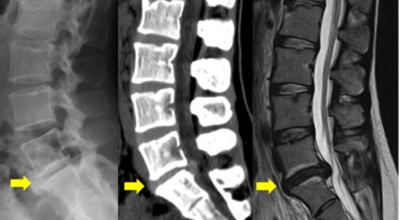

디스크 제거술

디스크 제거술은 현미경을 이용하여 파열, 돌출된 디스크를 없애는 수술로써 디스크를 직접 보면서 없앤다는 장점을 지니고 있다고 하며 다만 디스크 제거술은 작은 내시경 관을 통해 수술을 진행하기 때문에 수술 시야가 좁아서 완벽한 치료가 불가능하다는 단점을 갖고 있답니다.

골유합술 고정술

튀어나온 디스크를 없앤 뒤 그 자리를 메울 수 있는 보형물을 삽입하고 나사로 고정시키는 수술 방법으로 고정술을 통해 좁아진 신경을 넓힐 수 있을 뿐 아니라 척추의 안정성을 확보할 수 있어 수술 후 통증이 많이 적어지게 된다고 해요. 이 수술은 허리디스크가 너무 진행되어 다른 수술이 불가능할 때 시행하는 가장 최후의 수술 방법이라고 해요.

후궁 절제 척추관 감압술

허리디스크가 파열되지 않은 상태일 때 할 수 있고, 좁아진 척추관을 넓혀줘서 허리디스크를 치료해요. 감압술은 반드시 큰 부위를 절개하지 않아도 현미경, 내시경을 통해 수술이 가능하다는 장점이 있어요.